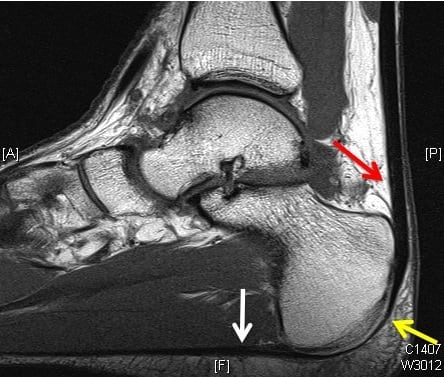

Для диагностирования повреждения используются инструментальные методы — МРТ или УЗИ. При подозрении на перелом или вывих проводится рентгенография. Лечение растяжения ахиллова сухожилия может быть как консервативным, так и хирургическим. При своевременном обращении к травматологу прогноз на полное выздоровление благоприятный.

Диагноз выставляется на основании осмотра поврежденной ноги травматологом. Рентгенологическое исследование при растяжении ахиллова сухожилия неинформативно, так как соединительнотканные структуры плохо визуализируются на полученных изображениях. Рентгенография проводится только при подозрении на сопутствующий внутрисуставной перелом или вывих. При необходимости пострадавшему назначают МРТ или КТ для оценки состояния ахиллова сухожилия, расположенных поблизости мягких тканей, нервов, кровеносных сосудов.